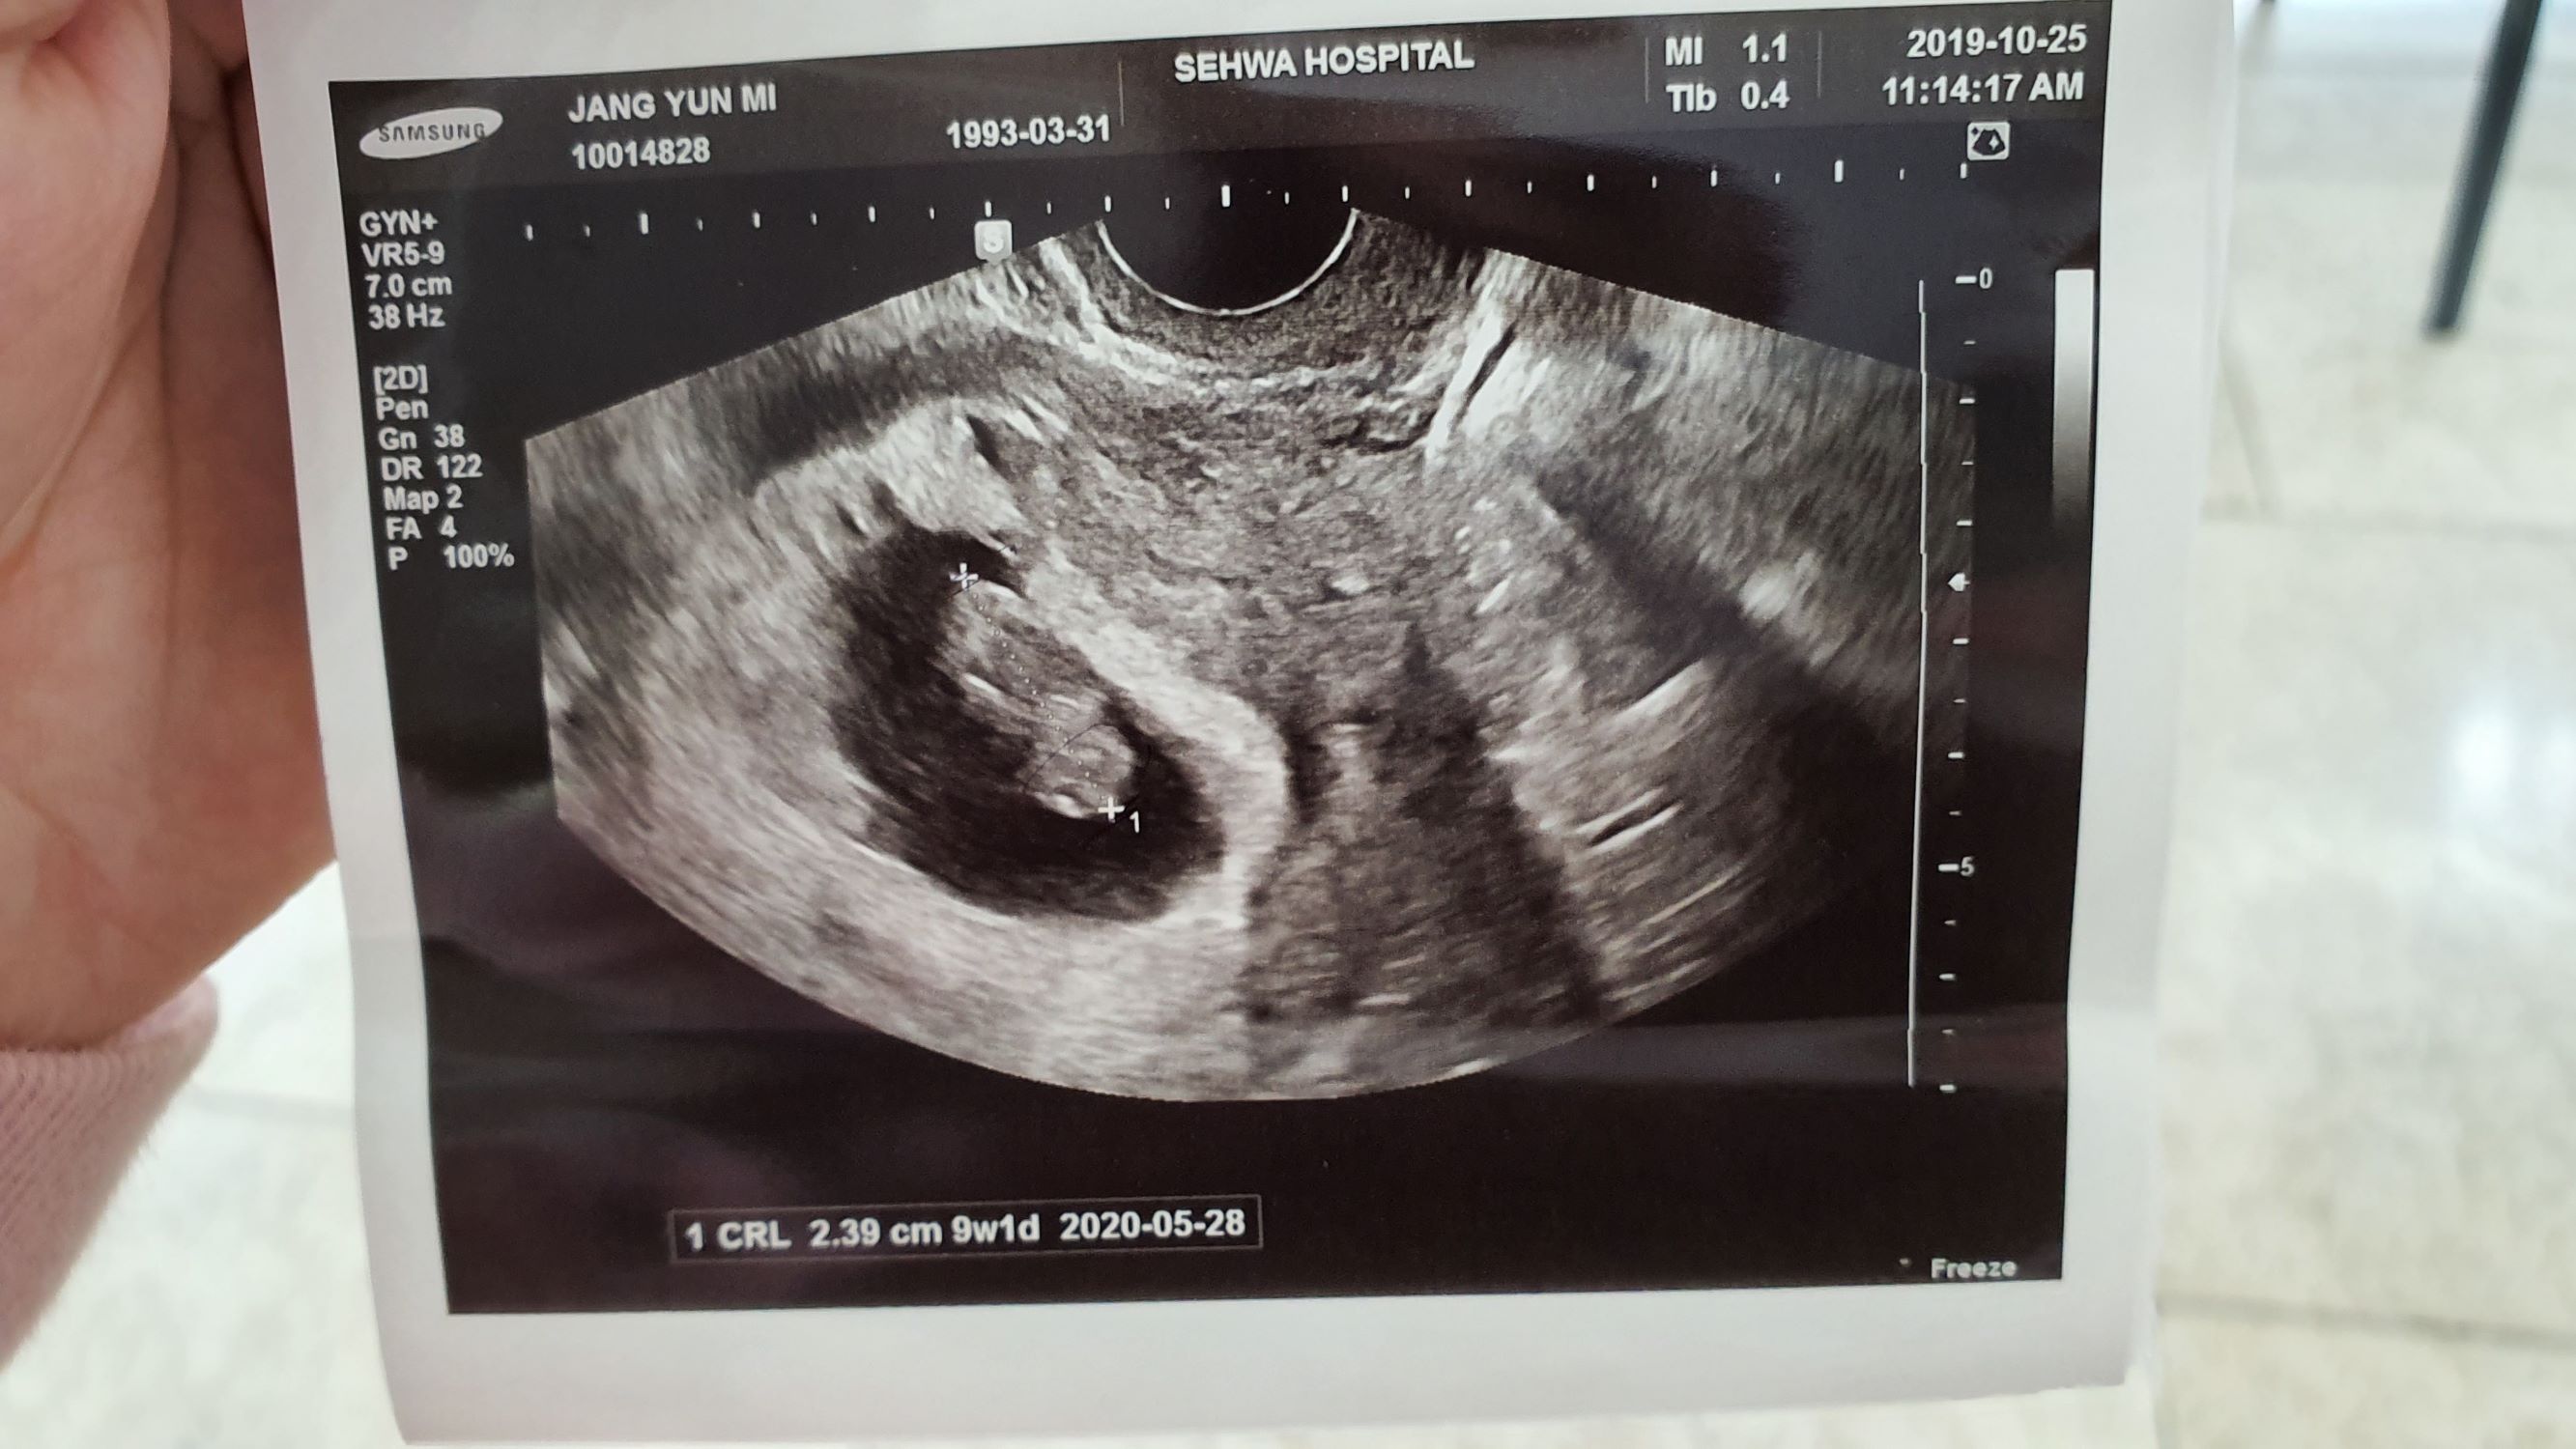

4b4919bf443cda3023a9baefc4c238f4_1572482698_3366.jpg

시험관을 결정해준 남편에게도 너무나 고맙고 한번만에 품으로 와준 아가도 너무 고맙고 정말 고마운 순간들이 넘쳐흐릅니다.

정말 너무나 감사한 순간순간이 지나서 벌써 이렇게 졸업을 앞두게 되어 성공후기를 쓰게되는 사실이 너무나 좋습니다만